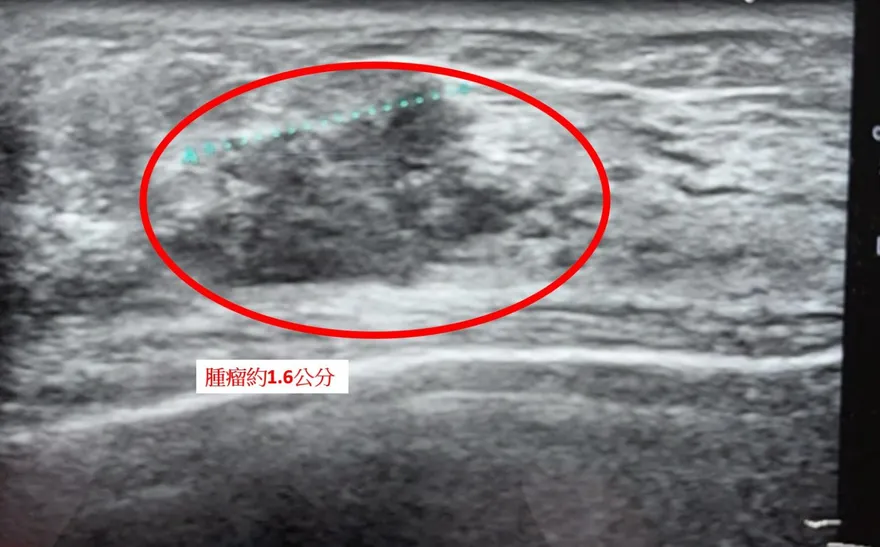

一側乳房三顆腫瘤!「全切除併雙側重建」術後5天上工

多發性乳癌

乳管原位癌